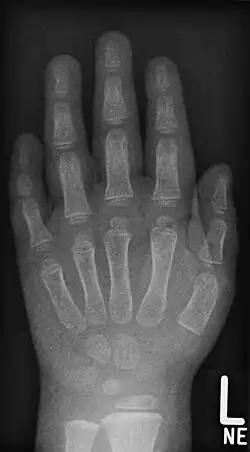

- Röntgenaufnahmen der Handknochen von Kindern unterschiedlichen Alters

-

Junge, 3,5 Jahre. Beachte auch die Brachymesophalangie am Kleinfinger -